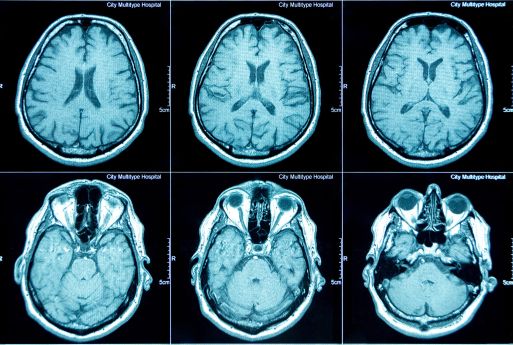

Redefining Early Diagnostic with Metabolic Imaging

The visualization of human metabolism allows for the detection of metabolic-related diseases in their earliest stages. By observing the metabolic processes at a cellular level, we can identify conditions such as cancer long before severe symptoms appear.

This breakthrough in early detection not only enables the identification of diseases at their most treatable stages but also accelerates treatment effectiveness. With real-time visualization of treatment responses, the progress of therapy can be directly monitored, ensuring faster and more effective intervention.